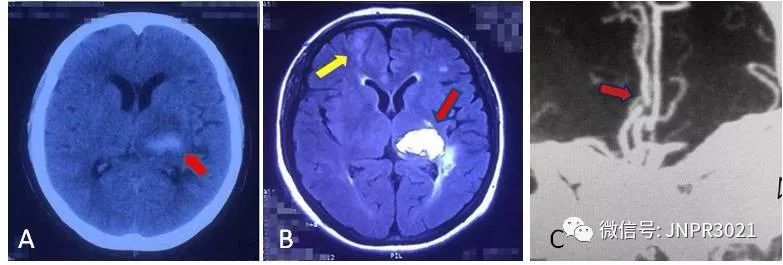

张女士,52岁, 病人有高血压病史,不规范的使用降压药,血压一直不稳定,波动很大。1个月前因突发脑出血右侧偏瘫,在当地医院治疗,病人好转后出院,遗有右侧面瘫和右侧肢体无力。出院1个月后,张女士又突发左侧肢体无力,伴言语含糊,赶紧来我院急诊。头颅CT提示除了左侧丘脑有个陈旧的脑出血灶外,在右侧额叶有一个脑梗死病灶,是导致这次左侧肢体瘫痪的责任病灶。病人入院时尽管意识清楚,但言语含糊,四肢瘫痪,双上肢肌力3级(正常人是5级肌力),双下肢肌力1级。入院后医生给她做了血管的评估,颈动脉彩超发现双侧颈动脉有动脉硬化斑块,血管造影证实右侧大脑前动脉严重狭窄致闭塞,这应该是本次脑梗死的主要原因。

上图A 首次发病时颅脑CT篇,红色箭头指示为脑出血病灶;图B 卒中复发颅脑MRI片,红色箭头指示原来的脑出血病灶,黄色箭头指示为新发脑梗死病灶;图C 脑血管造影图片,红色箭头示左大脑前动脉重度狭窄。